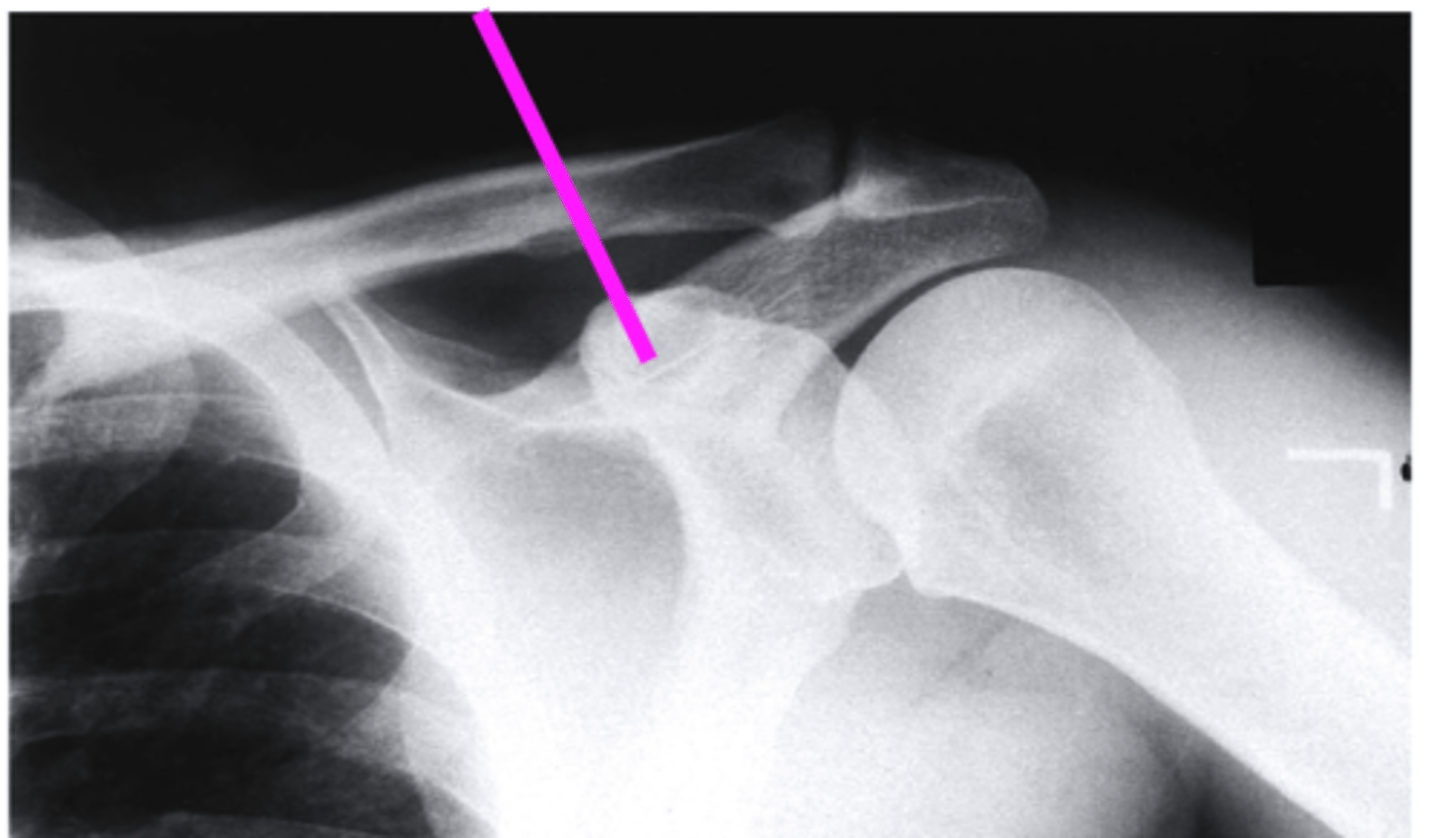

shoulder axillary

what view is this?

clavicle

what does the pink line point to?

the coracoid process

the glenoid fossa

acromion

humeral head